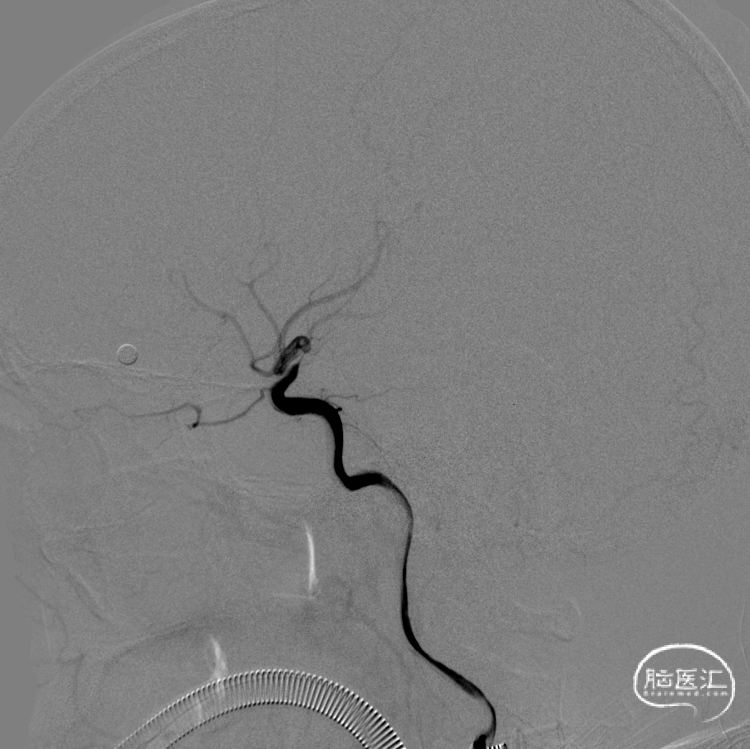

超选左侧颈内动脉造影显示:左侧颈内动脉末端极重度狭窄。

支架植入后左侧经总动脉造影提示:左侧颈内动脉末端狭窄明显改善,血管成形良好,前向血流明显改善。